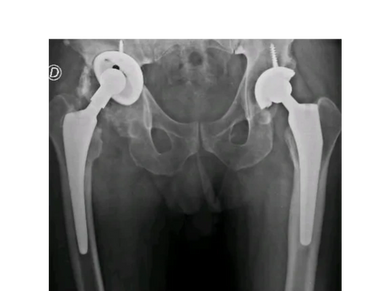

Cirugía de revisión por aflojamiento de prótesis de cadera con planificación 3D en Rosario - Dr. Pablo Mariani Rovea